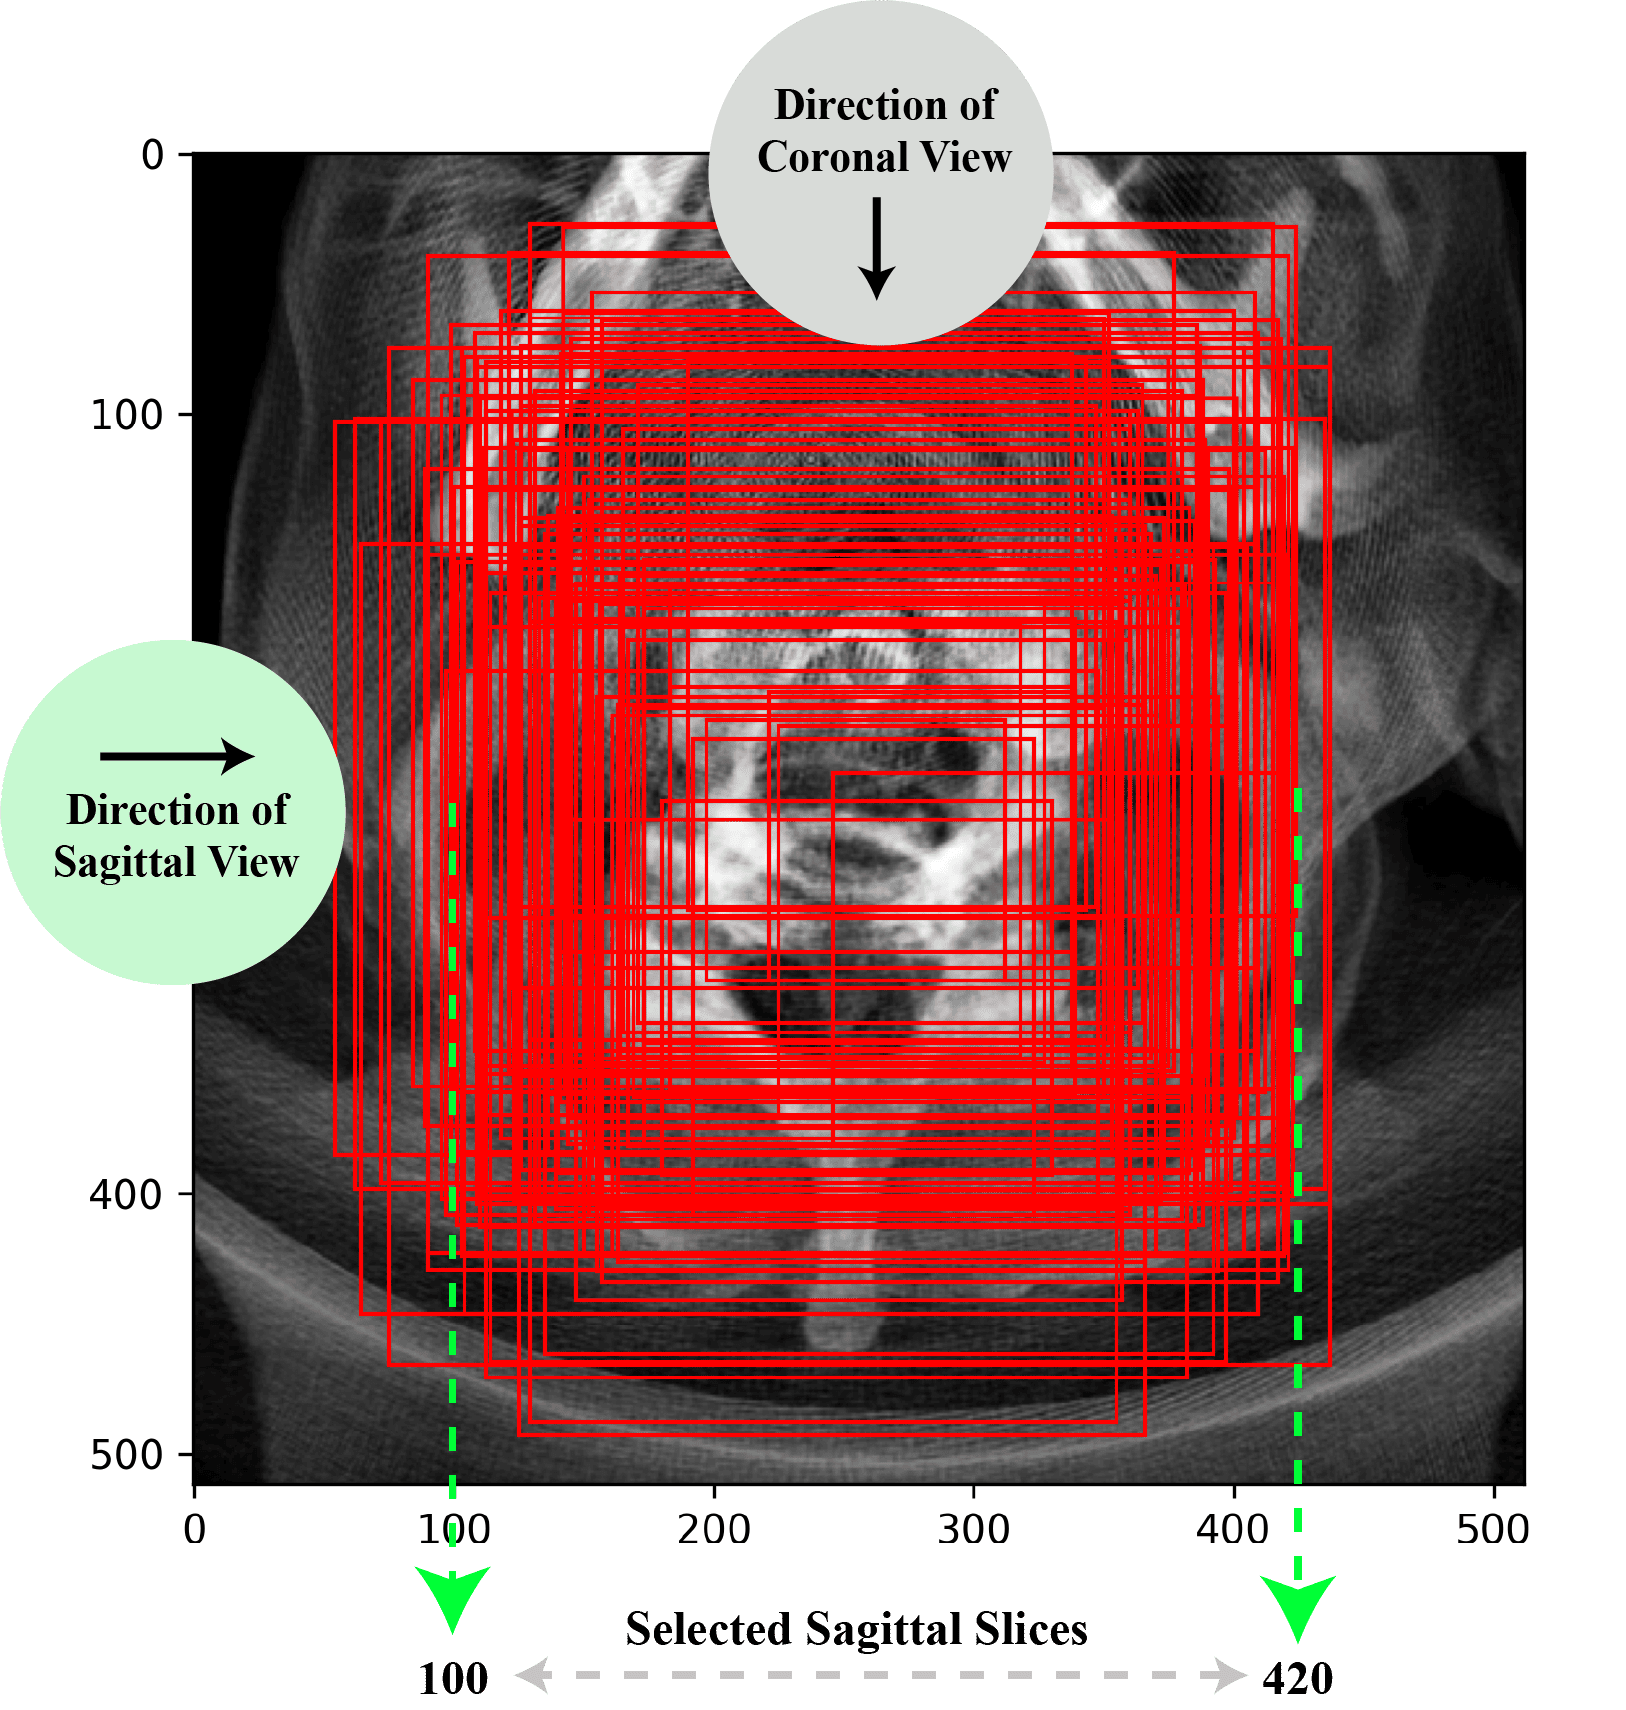

3.3.1 Sequential Slice Selection

To obtain the most accurate projection, it is essential to select slices that exclusively encompass the cervical spine. Therefore, a sequential slice selection approach was developed to achieve this efficiently. Initially, the bounding boxes for the given 87 patients were visualized. A common region in the center was identified based on where those 87 bounding boxes were. The upper and lower x-coordinates of these bounding boxes were identified, and a few outliers were excluded. These heuristically determined coordinates served as the baseline for all patients and were utilized to refine the sagittal selection. A sagittal slice range of 100–420 was selected for sagittal projection generation. A visual example of this heuristic sagittal selection is provided in Supplementary Figure S7.

Afterwards, the width of the sagittal bounding box for each patient was utilized to identify the corresponding coronal slices to generate a refined coronal projection. And finally, the axial slice range for a refined axial projection was determined by averaging the heights of the coronal and sagittal bounding boxes for each patient. This process is demonstrated with an example in Figure 6. The figure shows that at first the 100-420 slice range was used to generate a sagittal projection. Then the width of the sagittal projection 173-406 was taken as the slice range for the coronal projection. Then finally, the average of the sagittal and coronal bounding box height was utilized to get a slice range for the axial projection.